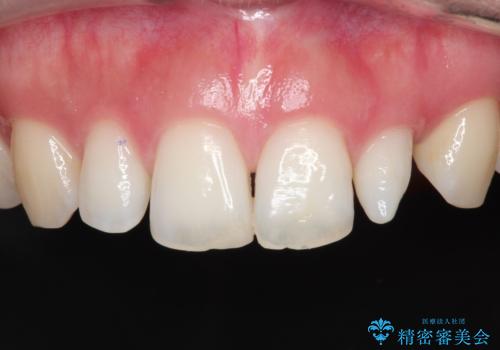

【オールセラミッククラウン】プラスチックの被せ物が壊れた。

- 以前他院で治療した被せ物が壊れたことを主訴に来院されました。

強度に優れたオールセラミッククラウンにて治療を行なっております。

3歯同時に治療を行うこと来院回数は4回で終了しています。